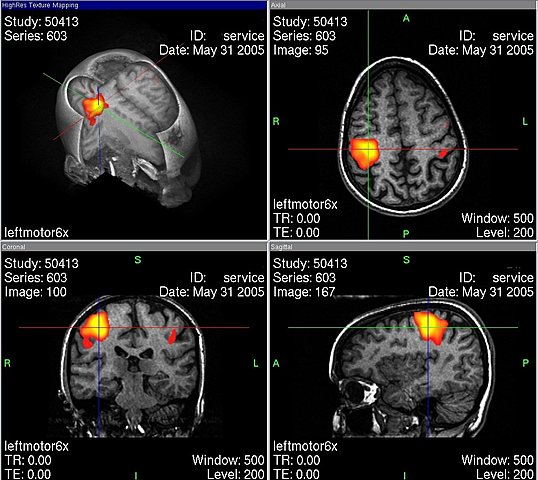

• RESONANCIA MAGNÉTICA FUNCIONAL

RESONANCIA MAGNÉTICA FUNCIONAL

1. 1900 – Se fortalece la investigación con el empleo de imágenes no ya anatómicas sino funcionales, en particular la resonancia magnética funcional (fMRI, por sus siglas en inglés) y la tomografía por emisión de positrones (PET), que permite visualizar la actividad cerebral durante la realización de diferentes tareas cognoscitivas (por ejemplo, hablar, leer, pensar en palabras etc.)